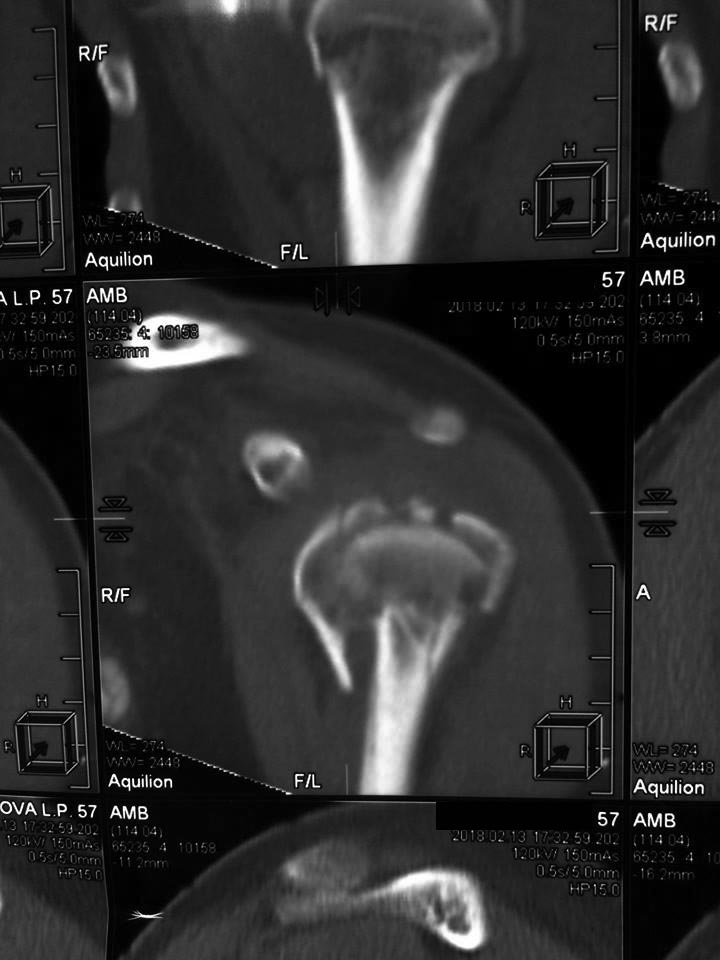

[Ortho] Перелом проксимального метаэпифиза плеча

Дорогие коллеги! Мнение о тактике лечения пациентки в нашем отделении

разделилось.

травма 10 дней назад, падение при катании на обычных лыжах. Сама

врач-рентгенолог 57 лет.

Левая рука, недоминатная. На данный момент ходит в косынке, вся в

сомнениях, что делать.

Мнения по лечению: - ничего не делать - остеосинтез пластиной

блокированной - первичное эндопротезирование (в наличие только геми,

delta не потянет) Может кто-то что более дельное предложит.